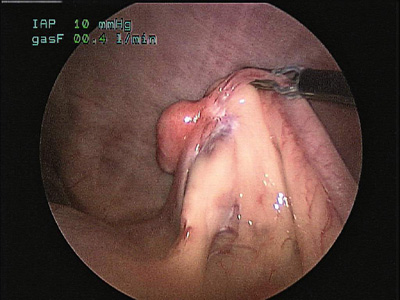

En lugar realizar ovariohisterectomias tradicionales, considere esta técnica, que se traduce en una recuperación más rápida y en menos dolor Por: Nicole J. Buote* La…